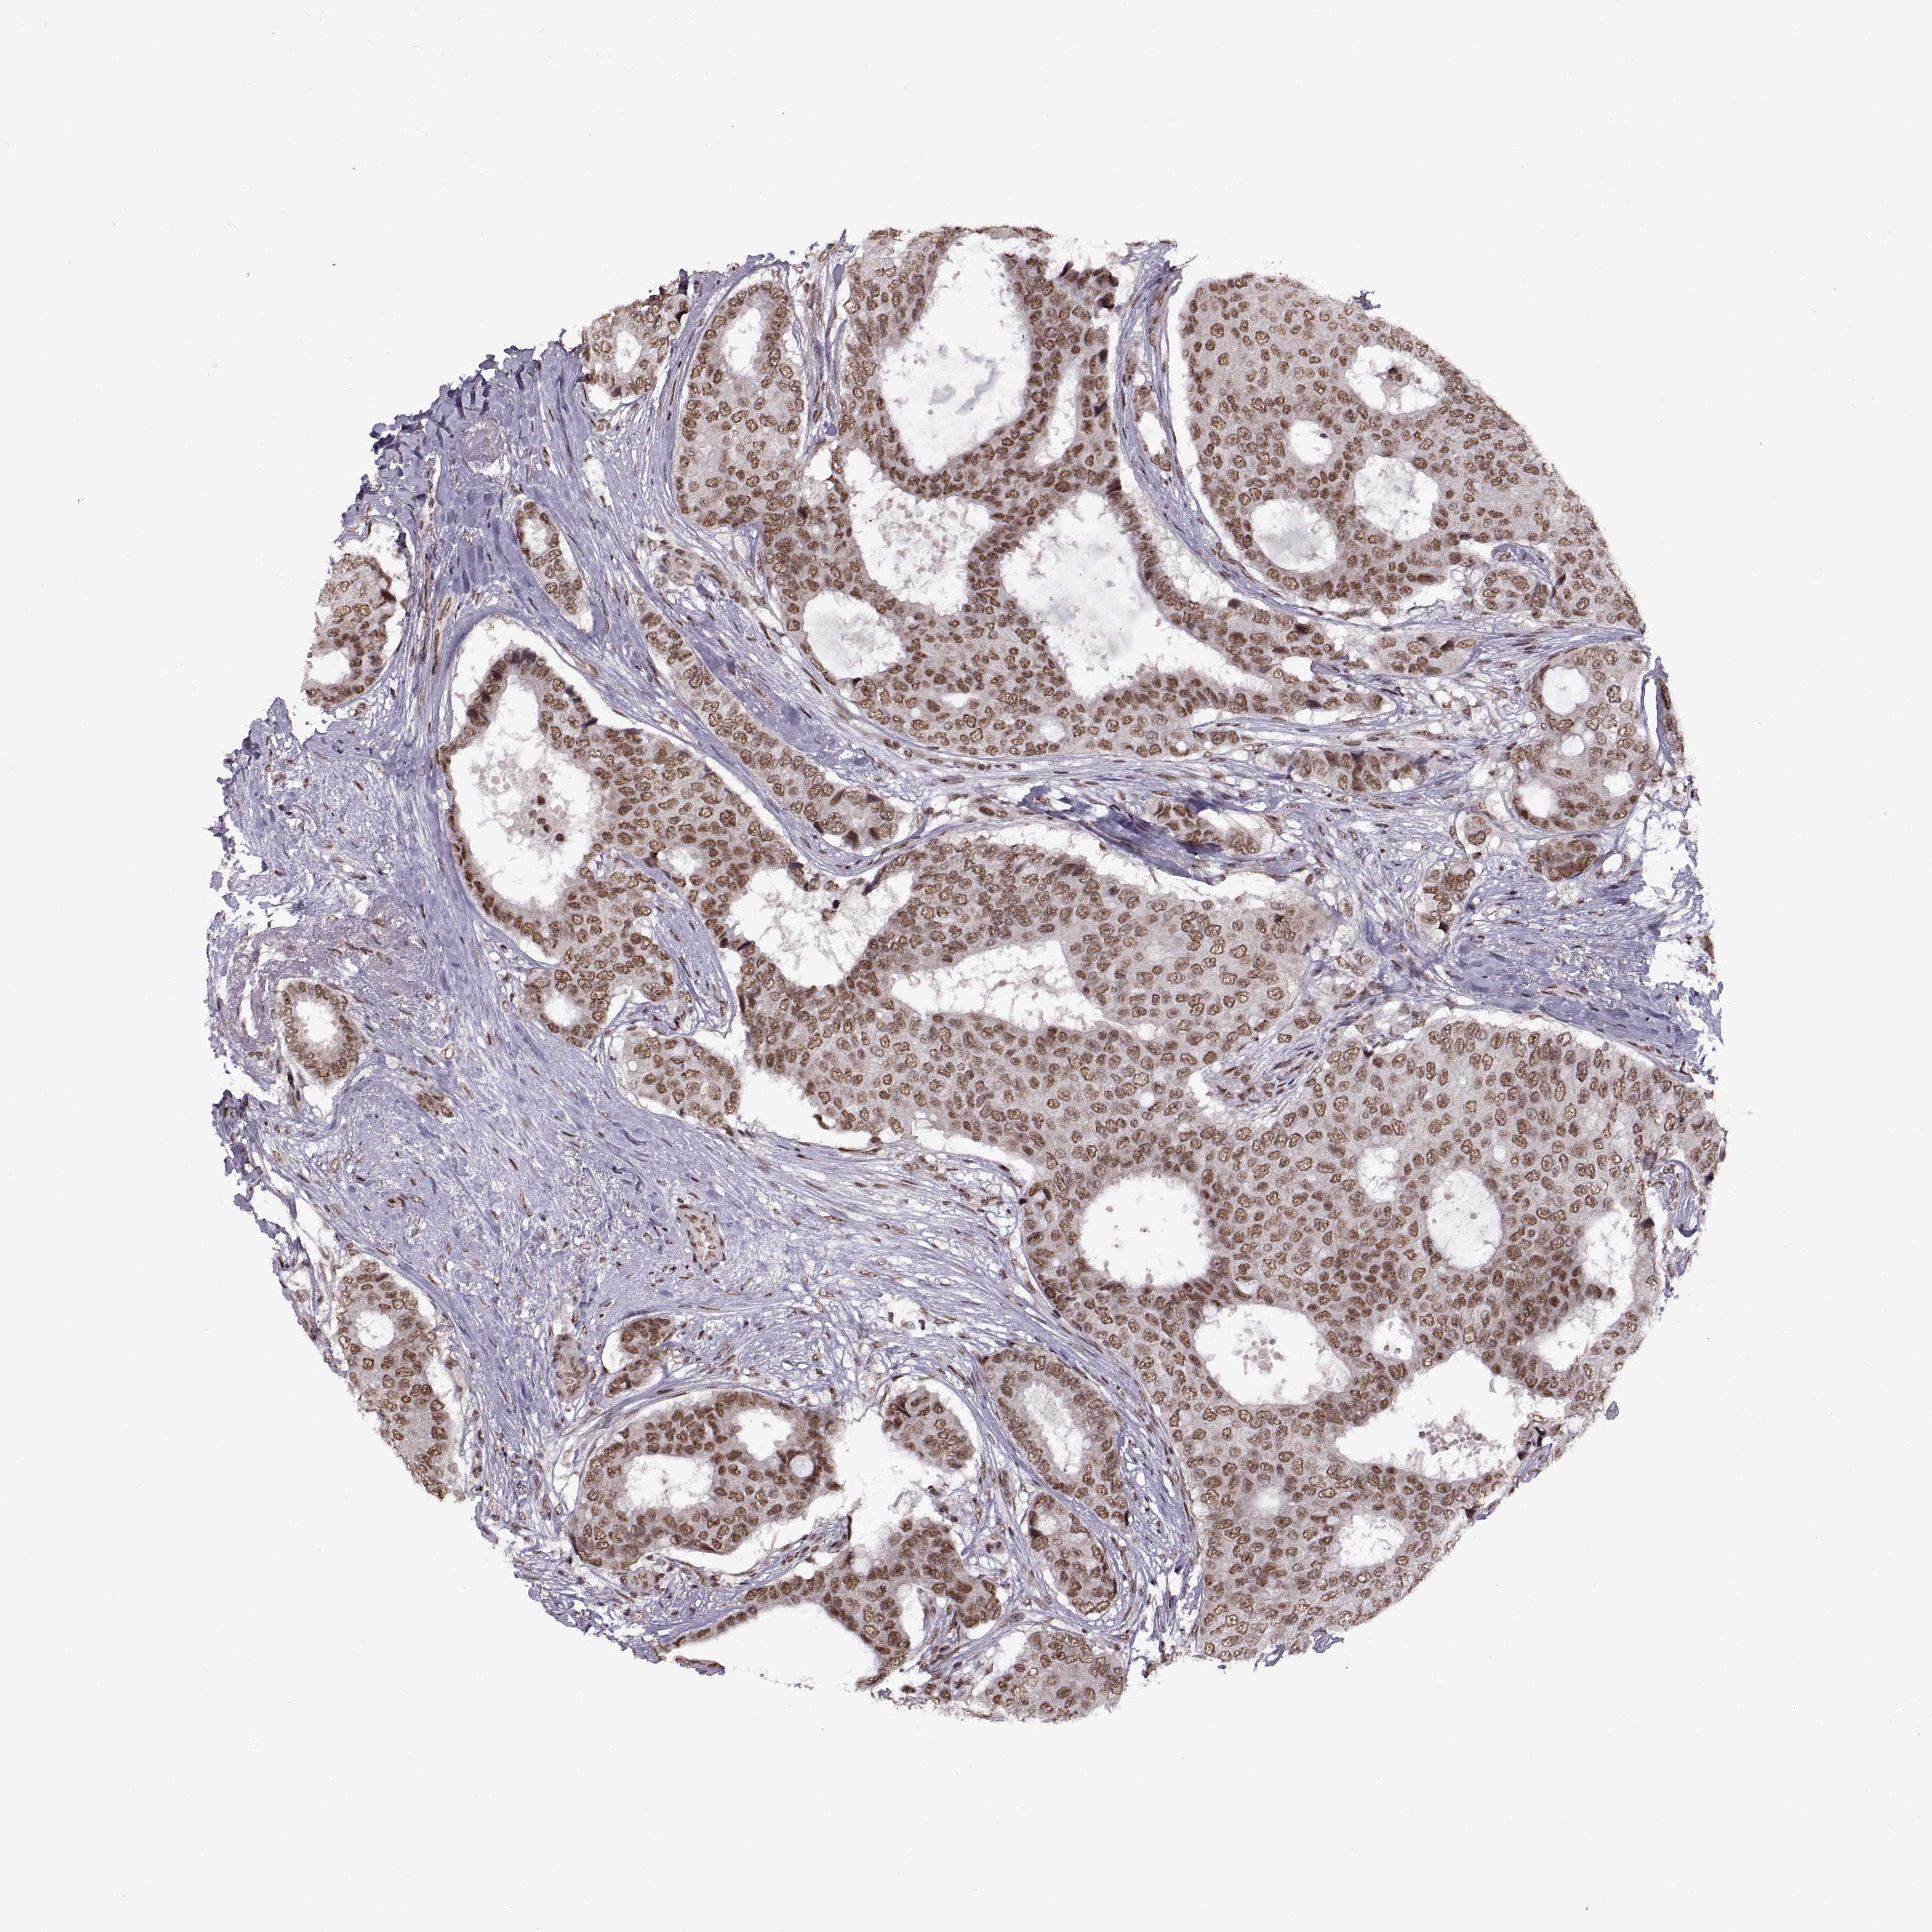

BRCA TCGA BRCA VALIDATION PROTEIN EXPRESSION